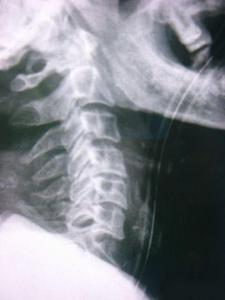

因為頸骨骨折也就是頸部脊椎骨的骨 折,在脊椎骨中央有神經(jīng)通過,這些神經(jīng)像電纜一樣能把大腦的命令傳達到全身,又能把身體的感覺傳向大腦。如果骨折切斷或壓迫脊椎骨中的神經(jīng),頸以下就會完 全麻痹,有時會使呼吸停止。

3、頸椎骨折常見于跳水誤跳入淺游泳池,或從很高的地方墜落以及交通事故等。